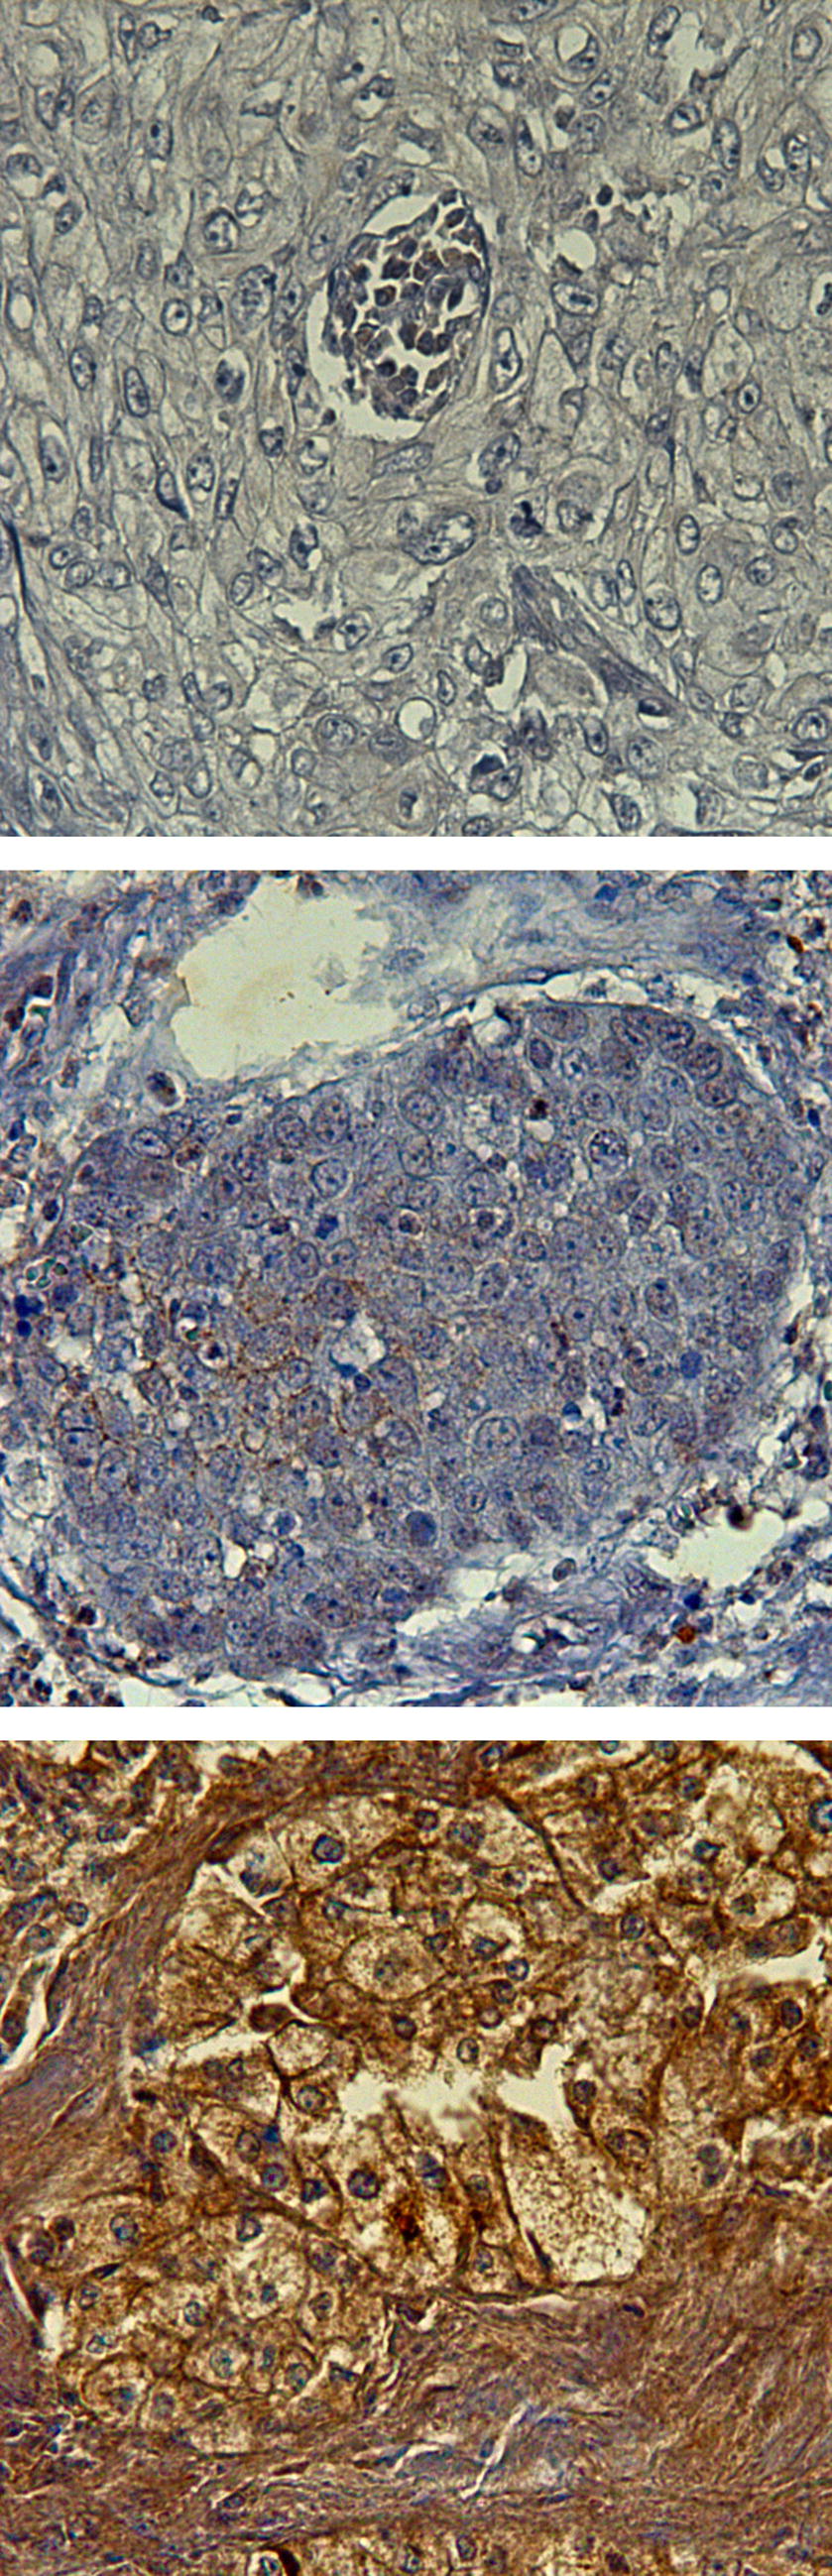

Fig. 1

Exemplary demonstration of varied immunohistochemical staining scores for B1-R. from top to bottom: B1-R immunoreactive score negative; B1-R immunoreactive score = 2; B1-R immunoreactive score = 5